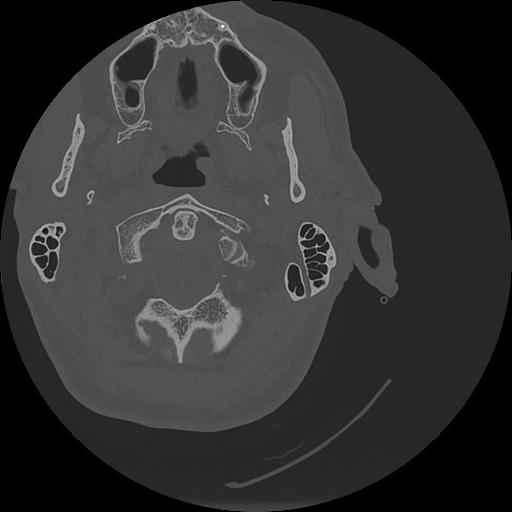

7 HUESO,,Vol,0.5,HUESO,,